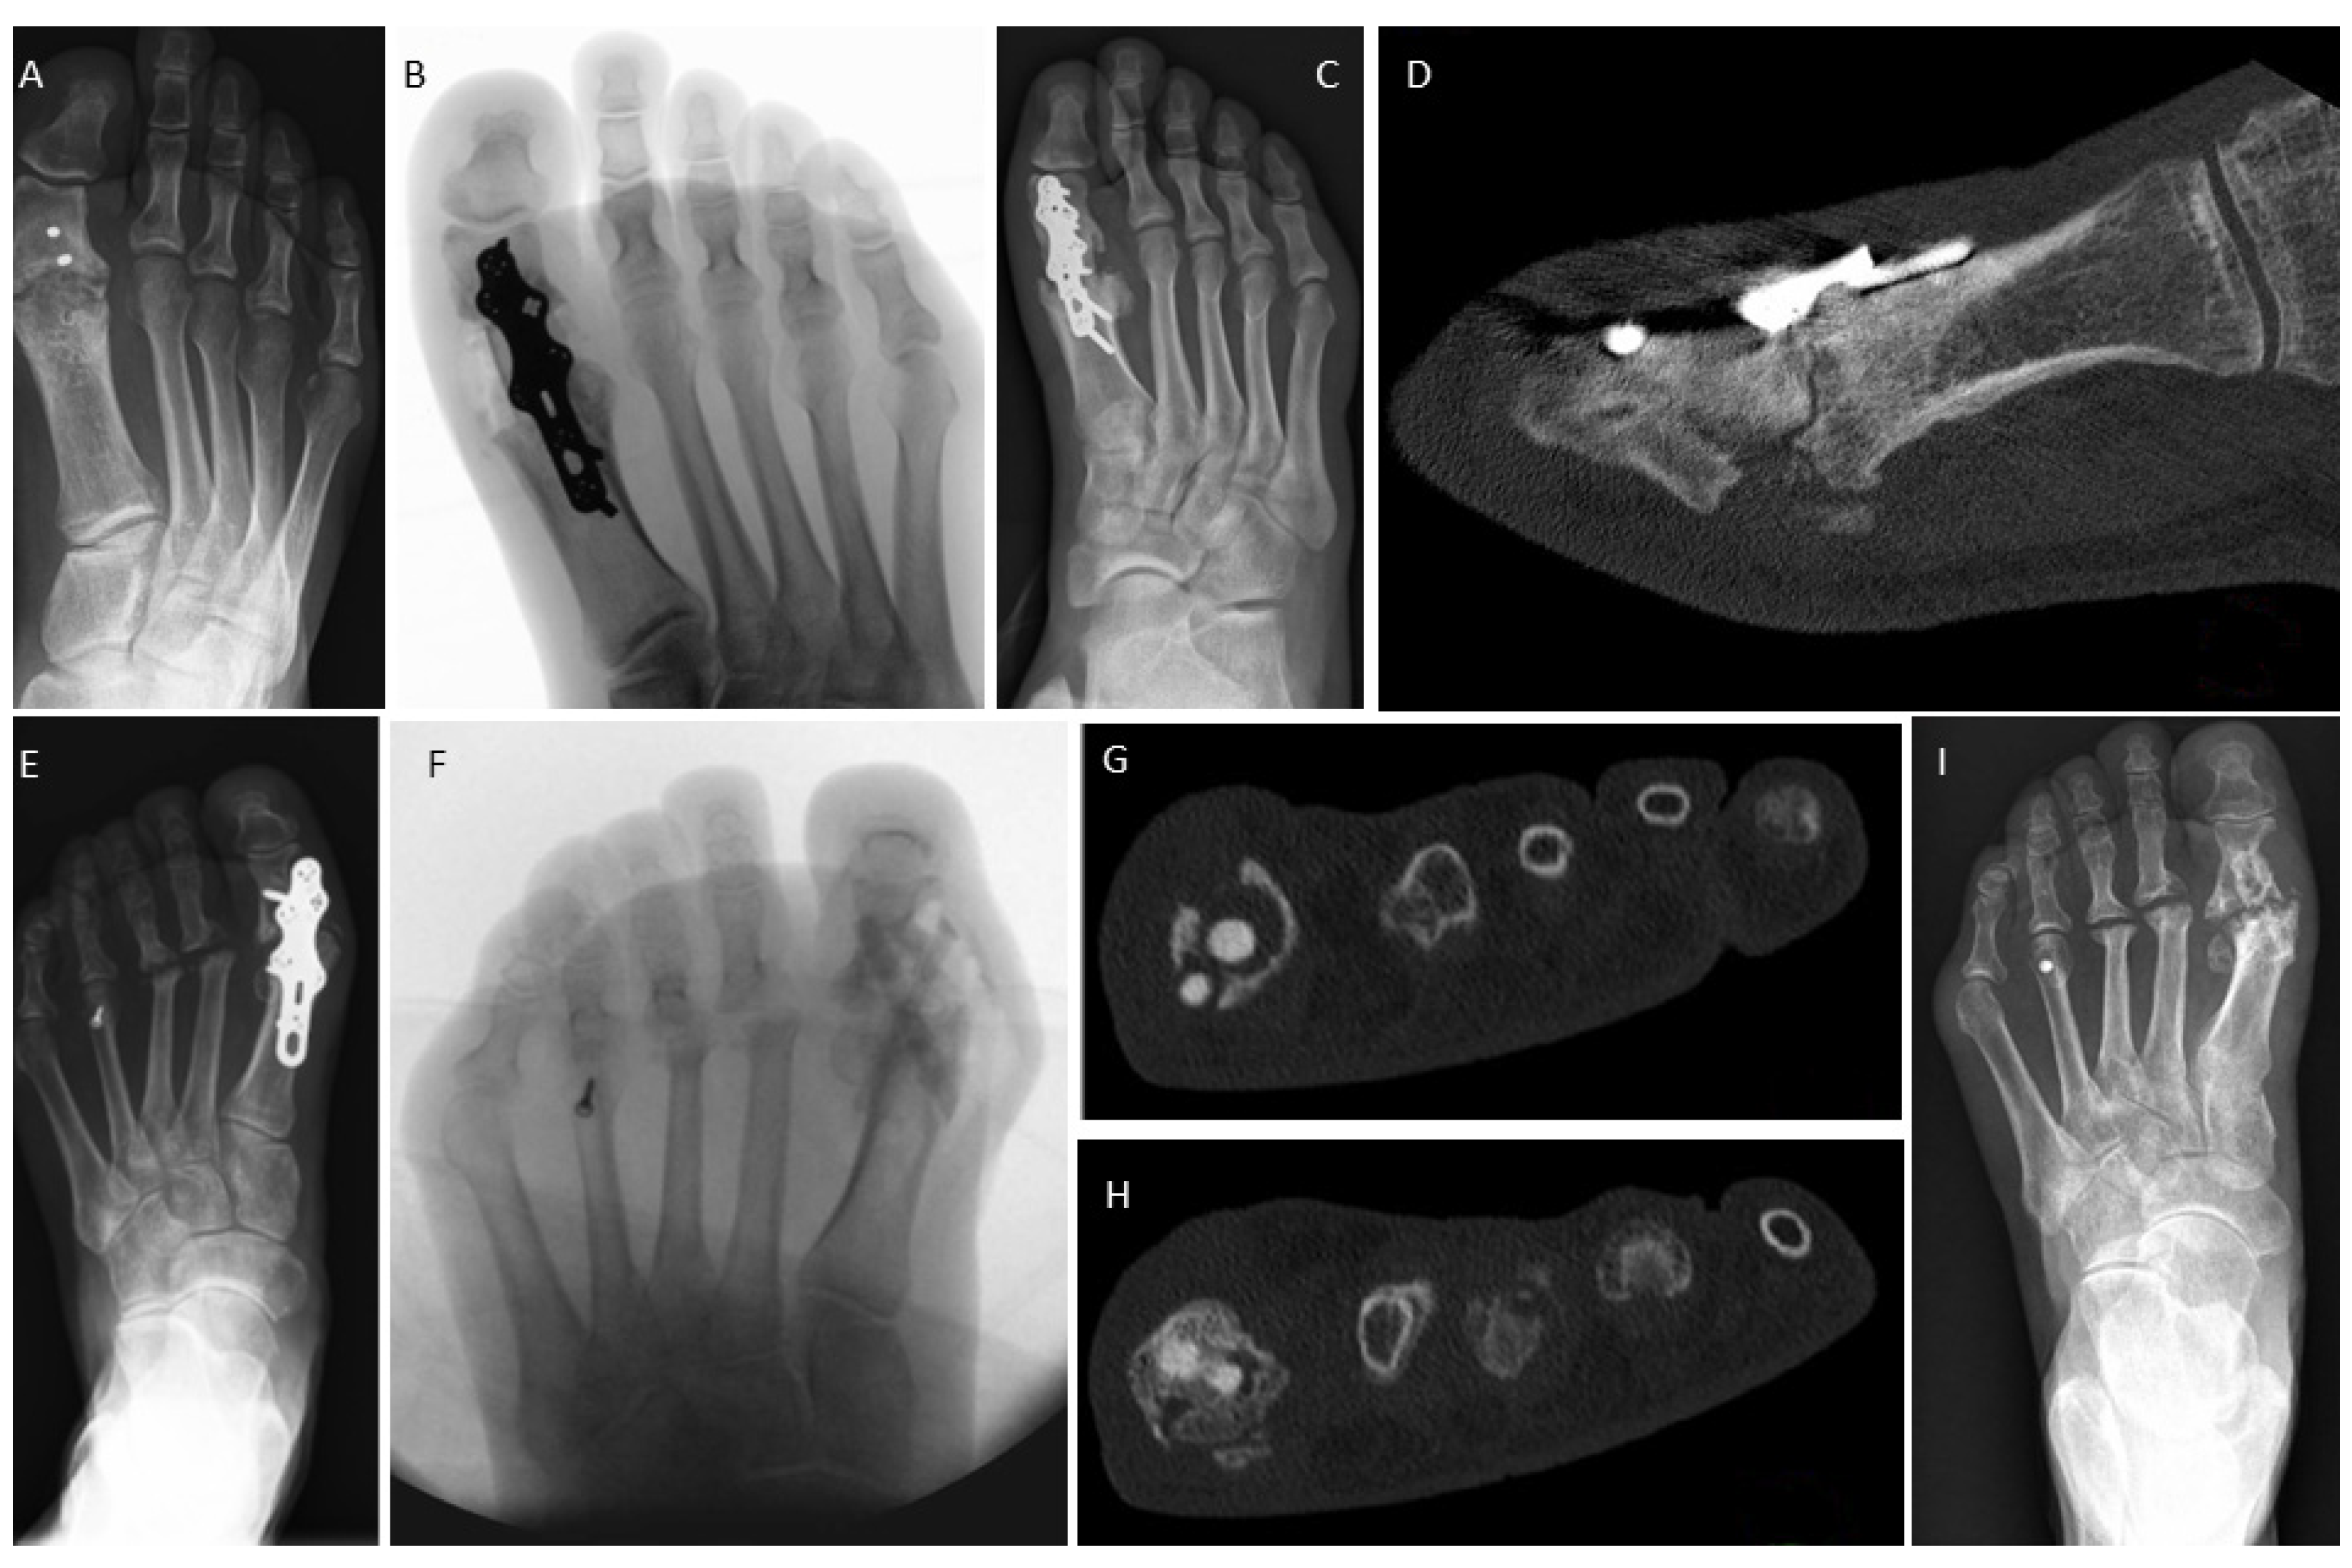

3.4. Examples for Bone Healing